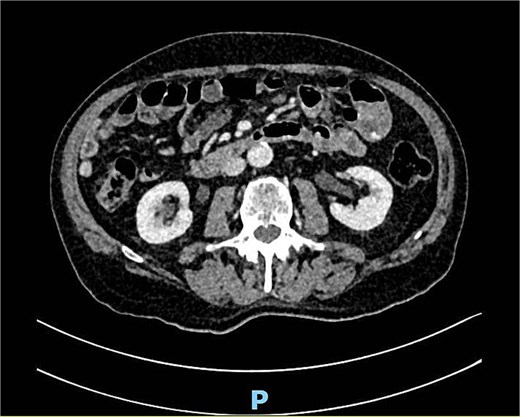

A computed tomography angiography (CTA) of the abdomen was performed, it showed a long segment of the small bowel with wall thickening in the right lower quadrant, accompanied by a inflammatory change in the mesenteric fat with multiple air bubbles, and free fluid in the pelvis, suggestive of hollow organ perforation (Fig. 1). Given the high suspicion of hollow organ perforation and clinical signs of peritonitis, an indication for exploratory laparotomy was established and performed as an emergency procedure. An antibiotic therapy with piperacillin/tazobactam was empirically initiated preoperatively.

CTA showing a long segment of small bowel with inflammatory wall thickening and fat stranding of the mesentery with multiple air bubbles.